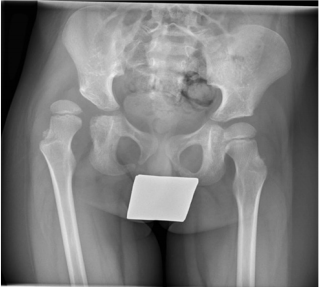

The MCPHCS was applied preoperatively and at an early followup 4 to 13 months postoperatively (median 9 months) based on AP pelvic radiographs. According to MCPHCS the parameters Reimer’s MP, femoral head deformity and acetabular deformity were evaluated. In addition, Rutz’ head shape classification [2] and the age- and sex-related percentiles of the acetabular index (AI) as recommended by Tönnis [21] were registered. For evaluation of the head shape one hip had to be excluded (n=70) and for the measurement of the acetabular index two more hips were excluded (n=69). These three patients had insufficient radiographs either preoperatively or at follow-up preventing assessment. JMP® version 13.1.0 was used for statistical analysis and visualisation. A representative case example of a 5 years and 5 months old boy who had a hip reconstruction right and VDO left is provided in Figure 1 (preoperative) as well as for the short-term (Figure 2) and midterm follow up (Figure 3).